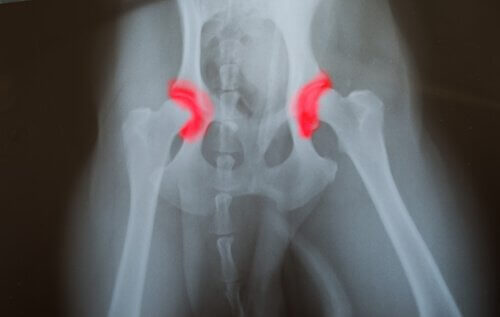

Displazi nedir?

Kalça veya dirsek displazisi kuşaktan kuşağa geçen kalıtsal bir hastalıktır. Eklemi oluşturan kemiklerin- ya kalça ya da dirsekte olur – doğru yerleştirilmemiş ya da hizalanmamış olmasından kaynaklanır. Bu onların birbirlerine sürtmelerine ve uygunsuz hareketler yapmalarına neden olur. Bu, eklemlerin arızalanmasına neden olan diğer sorunlara yol açan daha hızlı bir aşınmaya neden olur. Bu hastalıkla ilgili sorun sessiz bir hastalık olmasıdır.

Bu, problemin doğumdan beri bile uzun süredir var olabileceği anlamına gelir, ancak hayvan yaşamın sonraki aşamalarına kadar herhangi bir acı hissetmeyecektir. Bunu fark edeceksiniz çünkü evcil hayvanınız yemek yemekten ve zıplamaktan neredeyse hiç hareket edememeye kadar kötüleşecektir.

Genetik yapıları nedeniyle bu hastalığa yakalanma olasılığı daha yüksek olan bazı ırklar vardır. Bunlar çoğunlukla büyük köpeklerdir, çünkü eklemleri çok fazla ağırlık taşımak zorundadır. Ayrıca, bu tıbbi durum, hızlı bir şekilde büyüyen köpekleri etkiler, çünkü eklemlerini güçlendirmek için zamanları yoktur.